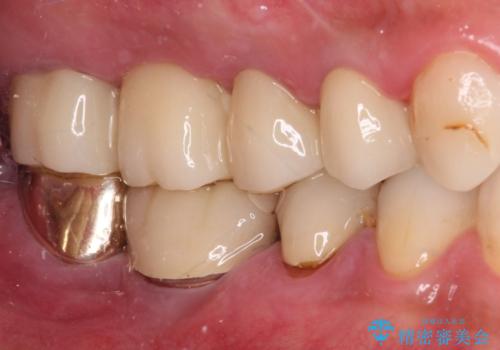

左側は大臼歯2本と小臼歯1本が欠損しているため、インプラント2本を治療したブリッジ、右側は中間欠損であり、前後の歯も加療が必要であったためブリッジによる補綴治療を行うこととしました。

治療後の現在は、より長い期間安定した状態を維持していただくため、就寝時マウスピースを装着するようお願いしております。